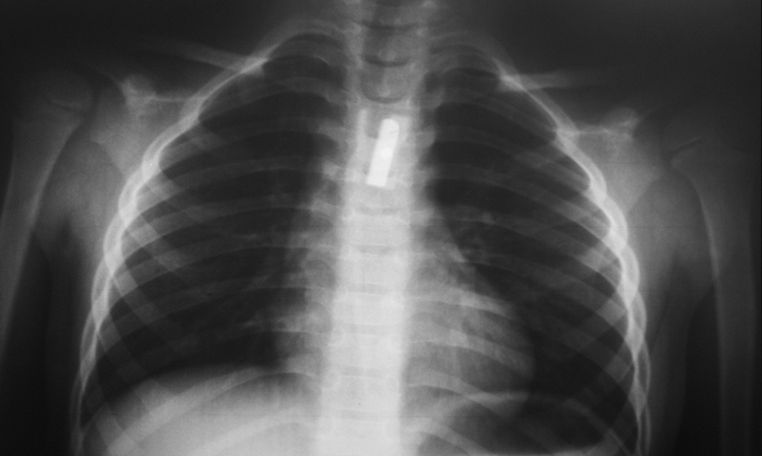

Cuerpo Extraño en Esofago